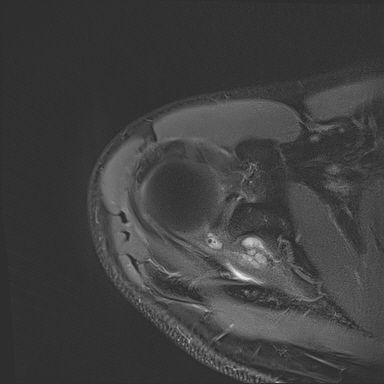

어깨 mri 좀 봐주세요 물혹있다고 하는데 수술해야 하나요?

하도 안 나아서 우측 견관절도 mri 촬영을 했는데 물혹이 있네요